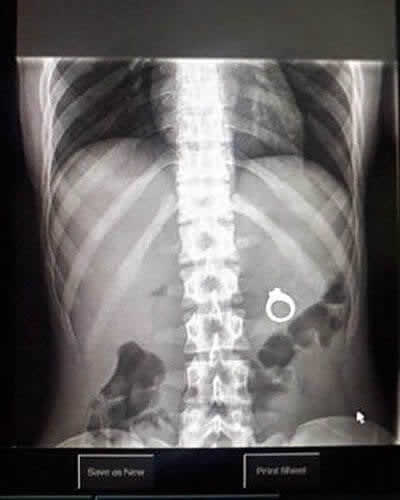

반지가 있을 곳이 아니네요

응급실은 늘 놀라움으로 가득합니다. 의료 전문가들은 모든 것을 보아왔고, 엑스레이 기계는 절대 거짓말을 하지 않죠. 사람들이 무엇을 삼키거나 몸속에 박히게 하는지는 정말 충격적입니다. 이 사진은 환자의 몸속 깊숙이 박힌 약혼반지를 보여줍니다. 이 반지가 어떻게 그녀의 내장 근처에 있게 되었는지는 오랜 미스터리입니다!

이것은 아마도 엉망이 된 저녁 식사 프러포즈로 보입니다. 파트너가 음료나 음식 속에 보석을 숨겼고, 그녀가 실수로 삼킨 것이겠죠. 부디 외과 의사들이 보석을 깔끔하게 회수했기를 바랍니다!